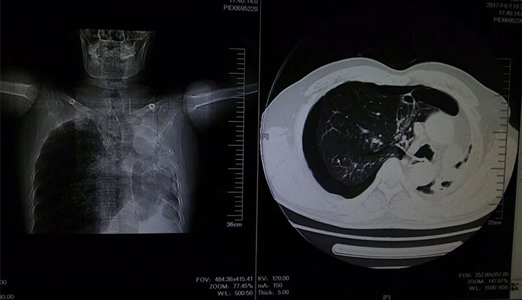

该患者为中年男性,胸闷,气促,休息后症状无缓解,来院就诊时全身大汗淋漓,口唇发紫,呼吸困难。临床医学院/附属医院医生询问病史后,发现该患者病情较复杂,且患者及家属对既往病史情况不太了解。考虑情况危急,当班医师立即组织抢救,给予吸氧、建立静脉通路及行胸部CT,同时请胸外科医师急会诊。经详细检查后,发现患者右肺自发性气胸,如不及时救治将危及生命。医务人员立即为患者做了右胸腔穿刺排气抢救,后给予胸腔闭式引流。在全体医护人员一个多小时的努力下,患者病情得到缓解,患者及家属对临床医学院/附属医院医务人员的精湛医术表示感谢。

张力性气胸来势凶猛,若抢救和处理不及时,则会危及生命。急诊科患者往往病史不详,且病史复杂多变、危及生命,带给医院及医生极大的考验。疾病的诊治需要多科室密切协作、相互补充,多学科齐心协作,才能最大限度提升救治水平,保障诊治效率和质量。该患者的抢救成功,体现了临床医学院/附属医院急诊科及心胸外科医护人员的快速反应能力和实践操作能力,同时也充分体现出多学科协作在急危重症抢救中的巨大作用。